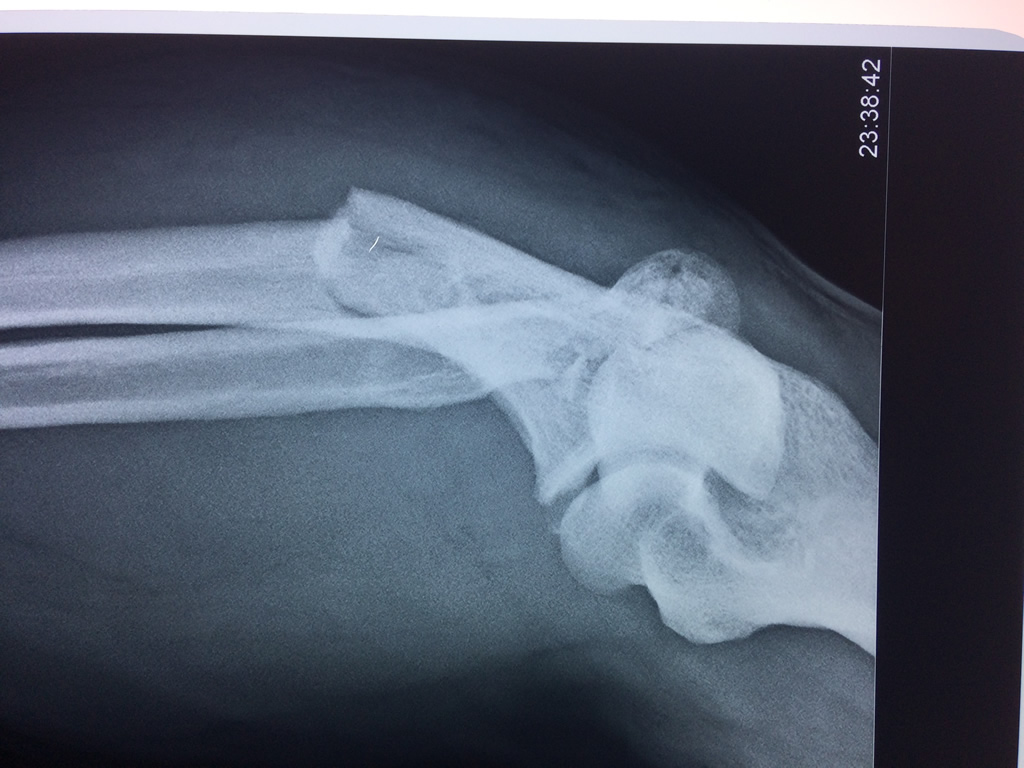

Cirugías de Hombros - Codo